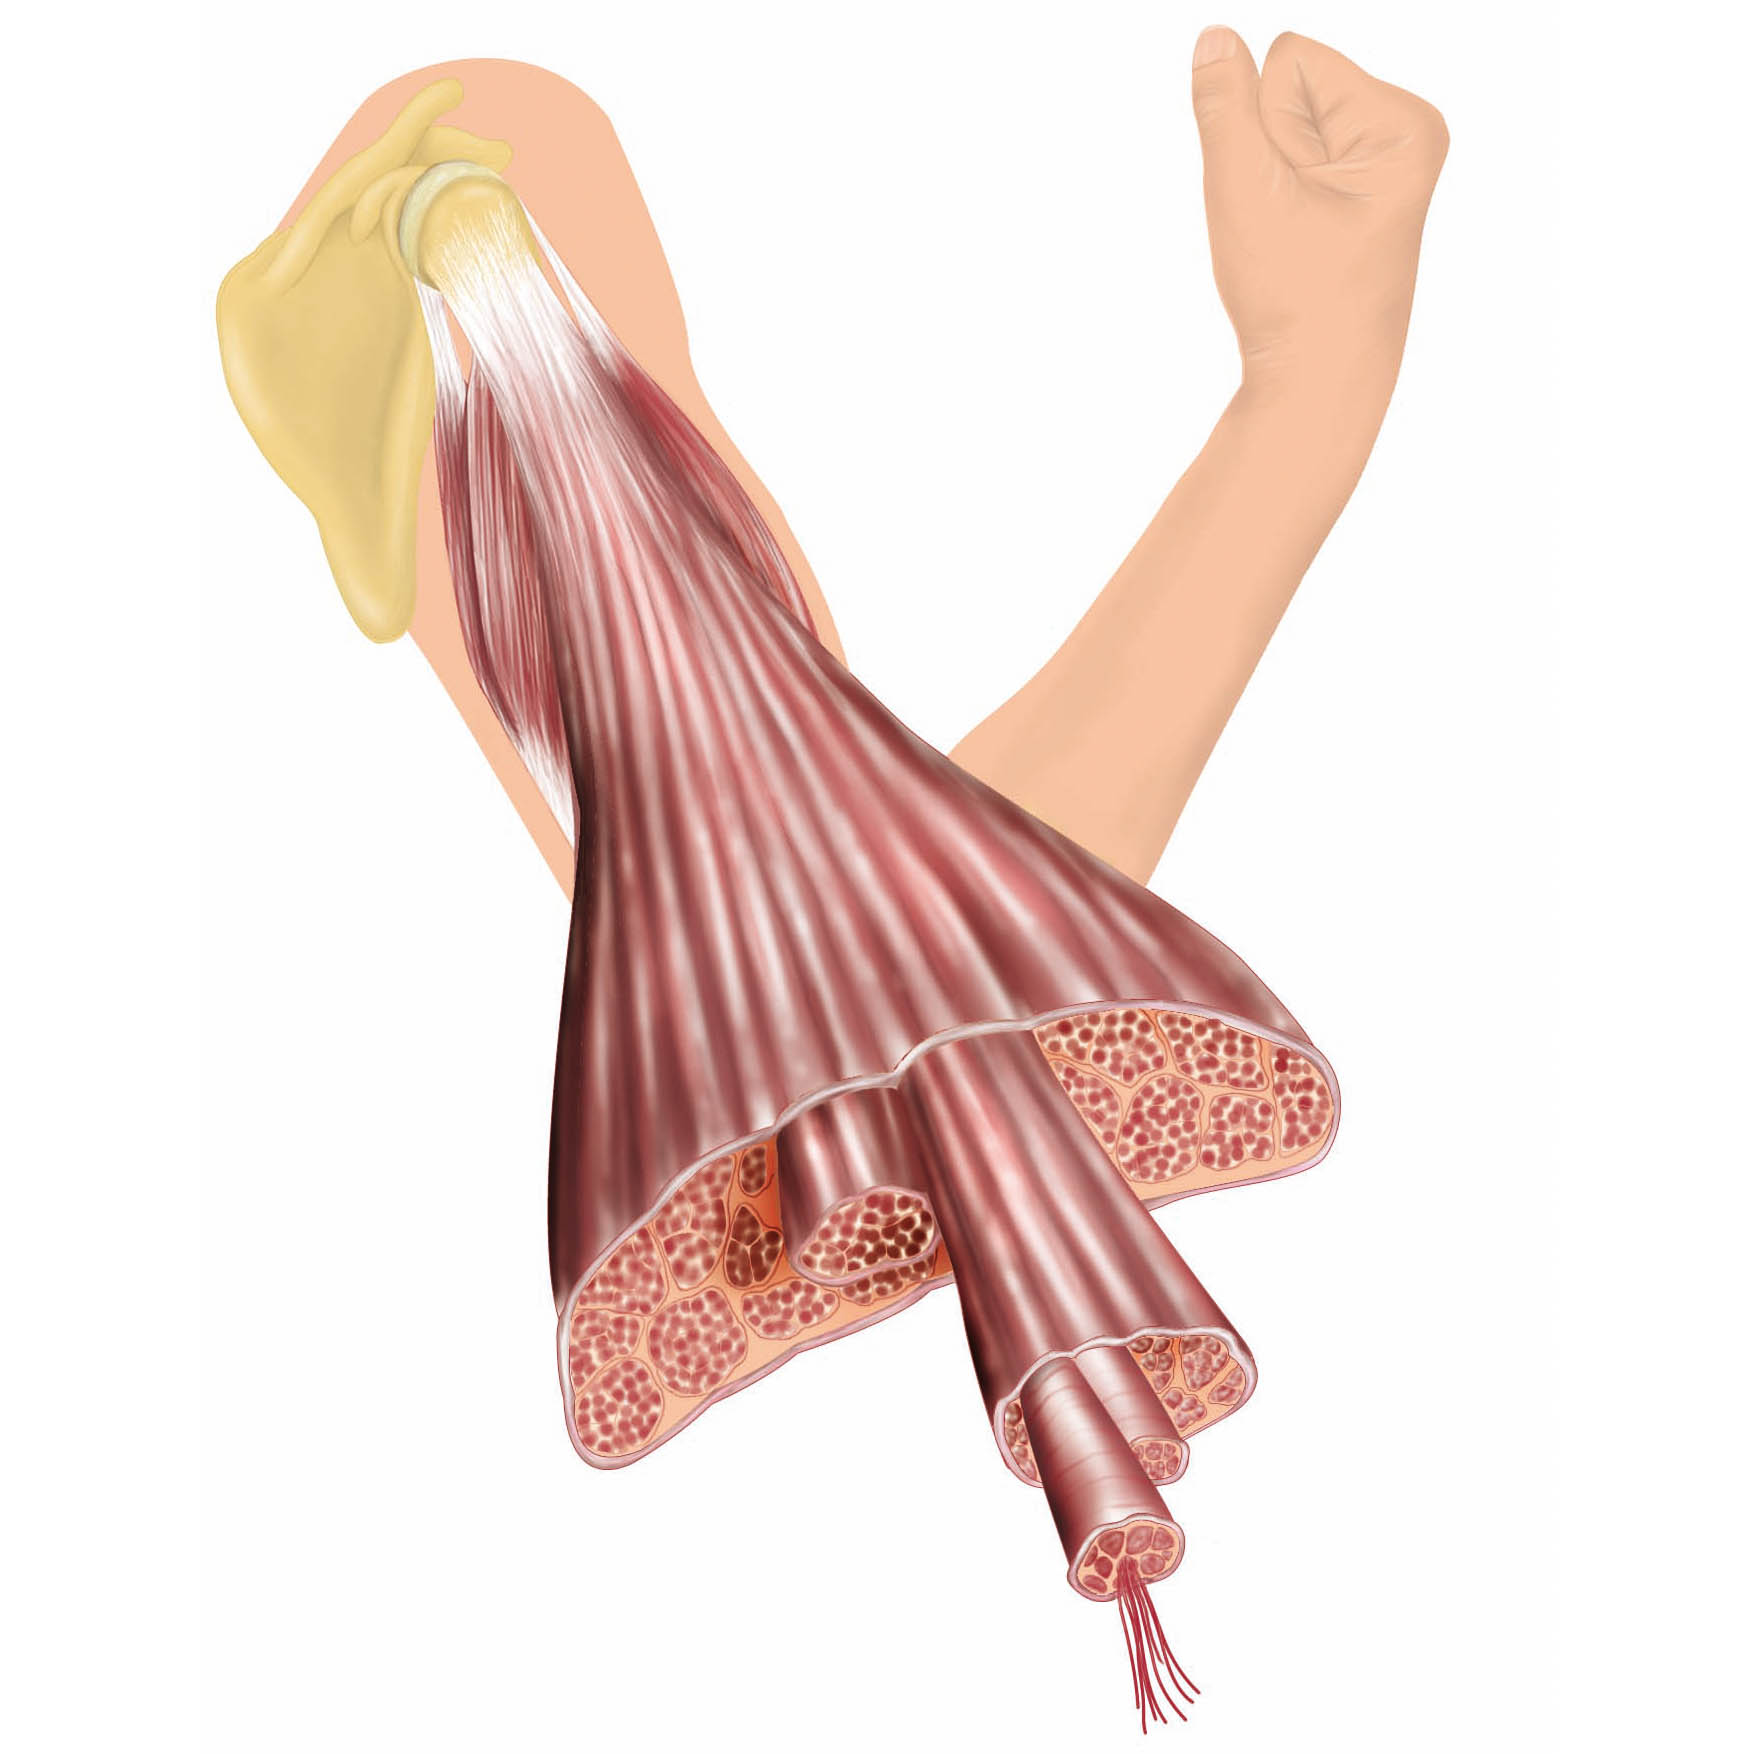

Herzlich willkommen! Ich bin Ihre Expertin für medizinische Illustrationen und kreative Kinderbuch-Illustrationen. Mit einem Auge für wissenschaftliche Genauigkeit und einer Liebe zur Gestaltung kindgerechter Erzählwelten schaffe ich Bilder, die informieren und begeistern. Entdecken Sie mein Portfolio und lassen Sie sich von meiner Arbeit überzeugen!